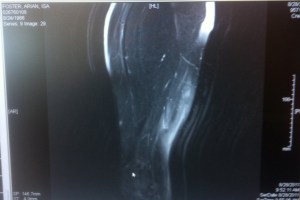

Today, in perhaps an NFL-first, a player tweeted his MRI. Earlier today, Houston Texans running back Arian Foster tweeted the MRI image of his injured hamstring.